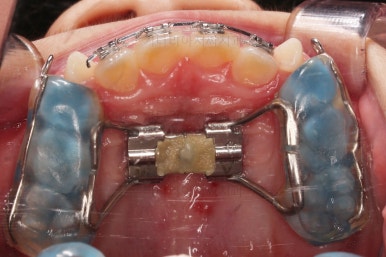

충분히 위턱의 성장이 완료되어 페이스마스크 치료는 종료하고 앞니 부분만 좀 더 가지런하게 해주기로 했어요.

치료 종료!

총 13개월 걸려서 부산초등학생교정 위턱의 3차원적 성장과 앞니 가지런함을 다 이뤘어요.

앞니의 반대교합 뿐만 아니라 어금니 반대교합도 개선되었네요.